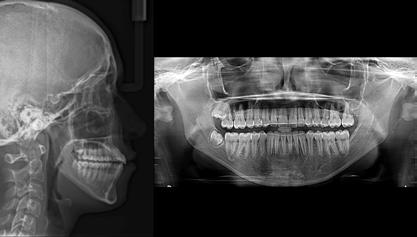

A 10 éves férfi páciens a felső frontfogai késői/nem megvalósuló előtörése miatt kereste fel a rendelőnket. A klinikai és a radiológiai vizsgálat során a jobb felső nagymetszőfog impakcióját észleltük (1. ábra). A fog horizontális tengelyállással és dilacerált gyökérrel rendelkezett. A felső dentális középvonal a fogak vándorlása miatt jelentős mértékben elcsúszott. A bal felső kismetszőfog is rendkívül kedvezőtlen pozícióba került.

Dr. Kazem Dalaie, dr. Samin Ghaffari, dr. Mazir Mir (Irán, Németország) 1. a ábra: Az intraorális felvételen jól látható a jobb felső nagymetszőfog lehetséges impakciójára utaló foghiány.

1. b ábra: A panoráma röntgenfelvételen megfigyelhető a teljes impakcióban lévő jobb felső nagymetszőfog. 1. c ábra: A CBCT felvétel is igazolja a jobb felső nagymetszőfog impakcióját.